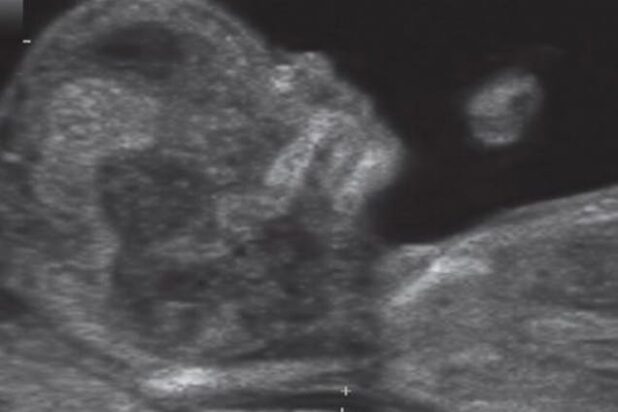

These are week 11 and week 12 scans: